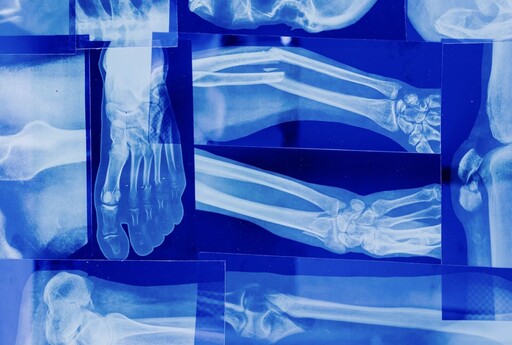

照片來源:示意照/翻攝自Pexels